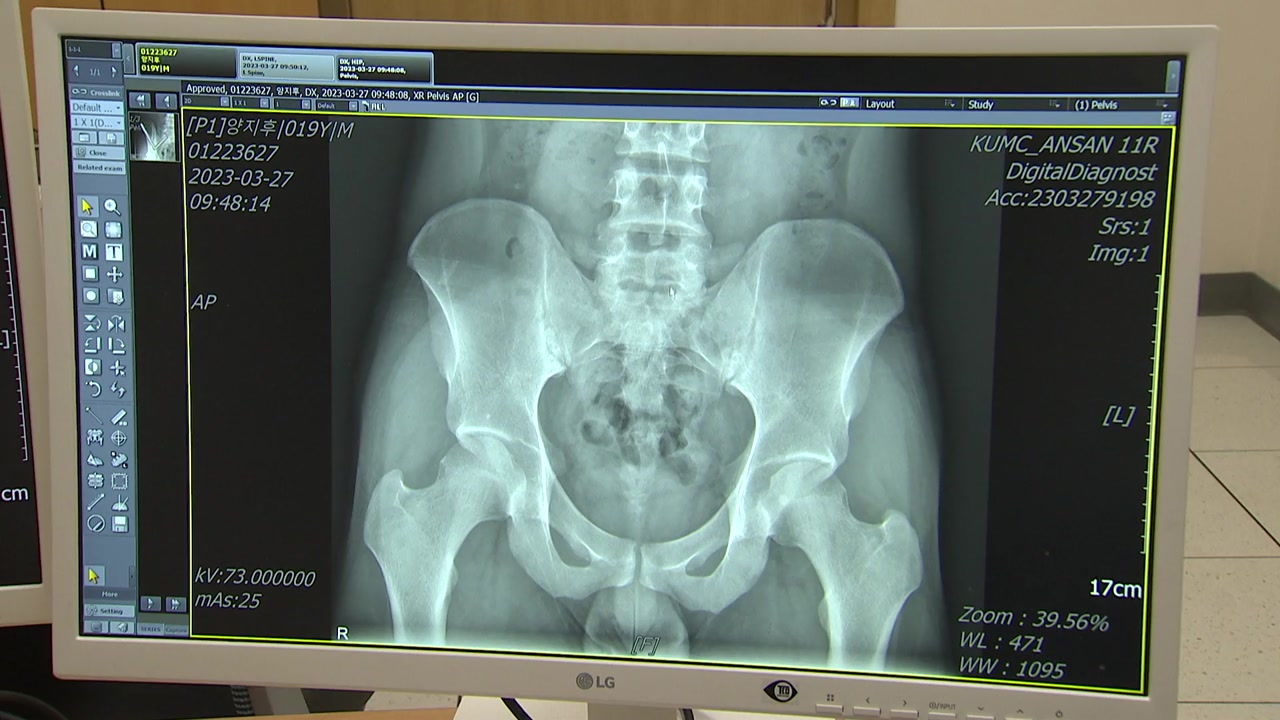

22살 양지후 씨는 어느 날인가부터 아침에 일어나면 묵직한 느낌과 함께 허리를 움직이기 힘들었습니다.

움직이다 보면 나아지는 듯해 별 것 아닌가 보다 생각했지만, 통증과 뻣뻣함은 거의 매일 아침 반복됐습니다.

알고 보니 양 씨는 강직성 척추염을 앓고 있었던 겁니다.

강직성 척추염은 면역에 문제가 생겨 척추와 골반에 통증이 나타나는 만성 염증성 관절염입니다.